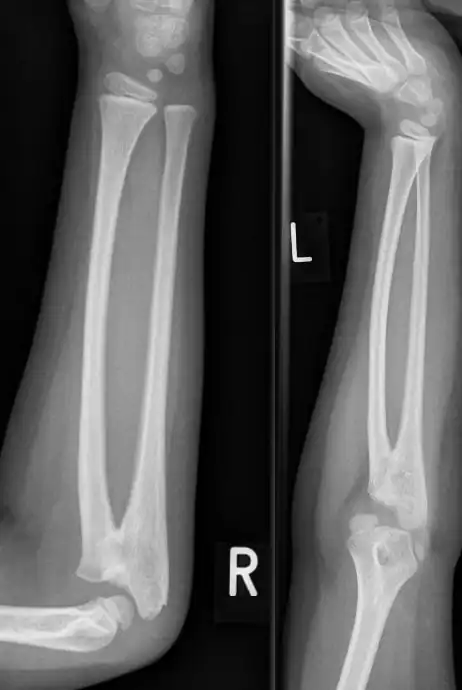

![]() Sinostosis radiocubital en un niño de 7 años. | ||

La sinostosis radiocubital congénita es una malformación congénita de los huesos del antebrazo, la cual se caracteriza por la fusión ósea anormal del radio y el cúbito.[1] Puede presentarse al nacimiento de forma congénita o a partir de una lesión traumática.

Esta condición es causada por una falla de diferenciación por parte del radio y el cúbito durante la vida fetal. Es decir, los huesos mencionados no se separan por completo durante la gestación y se encuentran fusionados al nacer.[4]